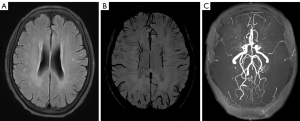

At the time of admission for query stroke in 2004, the patient’s initial brain magnetic resonance imaging (MRI) showed only a few small foci of white matter microangiopathic changes (Figure 1A), with no acute infarction on diffusion-weighted imaging (DWI) (Figure 1B). However, incidental time of flight-magnetic resonance angiography (TOF-MRA) findings of her brain demonstrated occlusion of the bilateral middle cerebral arteries (MCAs) and stenosis of the distal ICAs, with normal anterior cerebral arteries (ACAs) and posterior cerebral arteries (PCAs) (Figure 1C). She was diagnosed with severe intracranial atherosclerosis disease, which was managed conservatively with atorvastatin and aspirin. In the following years, the patient underwent regular imaging surveillance to monitor disease progression. Her recurrent TIAs raised concern, and clinicians considered whether it was feasible for her to receive more aggressive surgery or interventional therapy. In recent years, the condition of her vessels has been reevaluated by multi-sequence MRI, as she is allergic to iodine. The steno-occlusive severity of the patient’s intracranial arteries was assessed by MRA stages for MMD (7). The MRA stages were mainly determined by TOF-MRA maximum intensity projection (MIP) images, with source images used referentially. On the MRA, the steno-occlusive changes of the MCAs, ACAs and PCAs were graded as 3 stages (7): stage 1= no or mild stenosis (<50%), stage 2= moderate stenosis (>50%) but with intact distal segment, and stage 3= severe stenosis without any apparent distal segment. The patient’s moyamoya-type vasculopathy could be classified as stage 3. Surprisingly, the “ivy sign” was not very prominent on fluid-attenuated inversion recovery (FLAIR) images (Figure 2A). It is well known that the “ivy sign” is the result of the slow-flowing leptomeningeal collaterals that can be detected in MMD (8). Although the characteristic “puff of smoke-like” moyamoya vessels were not apparent, her bilateral PCAs were very thick and several branches could be seen originating from the bilateral PCAs and vertebrobasilar arteries (Figure 2B), which could be interpreted as evidence of the development of collaterals from the posterior circulation. High-resolution vessel wall imaging confirmed the intimal thickening and luminal occlusion of MCAs (Figure 2C). The patient’s overall imaging findings were not typical for MMD. With consideration to her medical history, the patient was eventually diagnosed with MMS by a multidisciplinary team (MDT) composed of neurologists, neurosurgeons and diagnostic and interventional radiologists.

The patient’s MDT initially considered intervention or revascularization surgery as the optimal treatment to reduce the frequency of recurrent TIAs and the risk of infarction. However, repeated ASL indicated that the patient’s cerebral hemodynamic impairments and collateral blood flow were not consistent with those of typical MMD. The patient’s ASL data were acquired with three-dimensional pseudo-continuous ASL (3D-pCASL) using the following parameters: labeling duration =1.5 s, postlabeling delay (PLD) =1.5/2.5 s, repetition time (TR) =3.7/4.7 s, echo time (TE) =11 ms, field of view (FOV) =240 mm × 240 mm × 85 mm, matrix =64×64, thickness =6 mm, and duration time =5 minutes and 21 seconds/6 minutes and 47 seconds. In 2013, the patient’s 3D-pCASL images showed serpiginous high signal intensity in the bilateral cerebral cortex and sulcus at a PLD of 1.5 s (Figure 4A), and, less prominently, in the bilateral temporal and parietal cortex at a PLD of 2.5 s (Figure 4B). From 2013 to 2020, 3D-pCASL at PLD of 1.5 and 2.5 s continuously demonstrated bright hyperintensity in the cerebral symmetric cortical surface. In 2021, the 3D-pCASL-based dynamic MRA referred to as “four-dimensional magnetic resonance angiography (4D-MRA)” and 3D-pCASL were performed on a new 3.0-Tesla MRI scanner (Ingenia CX, Philips) using 32-channel head coils. The latest ASL images showed hyperintense signal bands in the bilateral hemisphere at a PLD of 1.5 s (Figure 5A) and, much more prominently, at a PLD of 2.5 s (Figure 5B). Meanwhile, 4D-MRA data were acquired with the time-resolved angiography non-contrast-enhanced (TRANCE) technique using the following parameters: TR =9.3 s, TE =4.8 s, FOV =210 mm × 210 mm × 80 mm, spatial resolution =1.2 mm × 1.2 mm × 1.3 mm, matrix =172×130, thickness =1.3 mm, label delay =200 ms, label gap =20 mm, phase interval =200 ms, phases =10, and duration time =2,200 ms. Symmetrical emergence of bilateral PCAs was observed, and intracranial collaterals originating from the bilateral PCAs were clearly shown on the dynamic 4D-MRA (Figure 5C).

Between 2013 and 2020, the intensity of ATA on the patient’s ASL images at a PLD of 1.5 s was much more significant than that of 2.5 s, which suggested that the antegrade blood flow was comparatively faster. The latest ASL in 2021 showed that the intensity of ATA at a PLD of 2.5 s was much more intensive than before, which may suggest that the arterial transit time of the collaterals is longer than the anterograde blood flow. ATA is dependent on the arterial transit time and is influenced particularly by the labeling time and PLD. The decreased and slow blood flow might induce an ATA; therefore, cortical flow in moyamoya patients may resemble this hemodynamic status. The strength of the ATA alters according to the PLD value because the delayed blood flow due to stenosis or occlusion still remains in the cortical surface (24,27). Regarding this patient, ASL acquisitions with both shorter and longer PLD dramatically demonstrated conspicuous ATA in the bilateral hemispheric cortex, and this status has lasted almost 10 years to date. ATA has been reported to correlate with the development of collateral circulation and to reflect the presence of leptomeningeal collaterals on DSA (28). The balance of hemodynamics and compensated perfusion of this patient relies on slow flow from the collaterals of the posterior circulation, which prolongs the mean transit times of arterial blood flow and creates ATA on 3D-pCASL images. 4D MRA is a 3D-pCASL-based dynamic MRA with long labeling duration, which can ensure visualization of the complete arterial trees from proximal to distal vessels with adequate image quality (29). The patient’s latest 4D-MRA clearly shows the presence of collaterals mainly from the bilateral PCAs. Consequently, preservation and improvement of collateral blood flow can provide protection against future strokes and reduce the frequency of ischemic symptoms while effecting a concurrent reduction in collaterals.